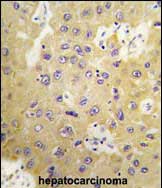

IHC 1/100-1/500 Human,Mouse,Rat